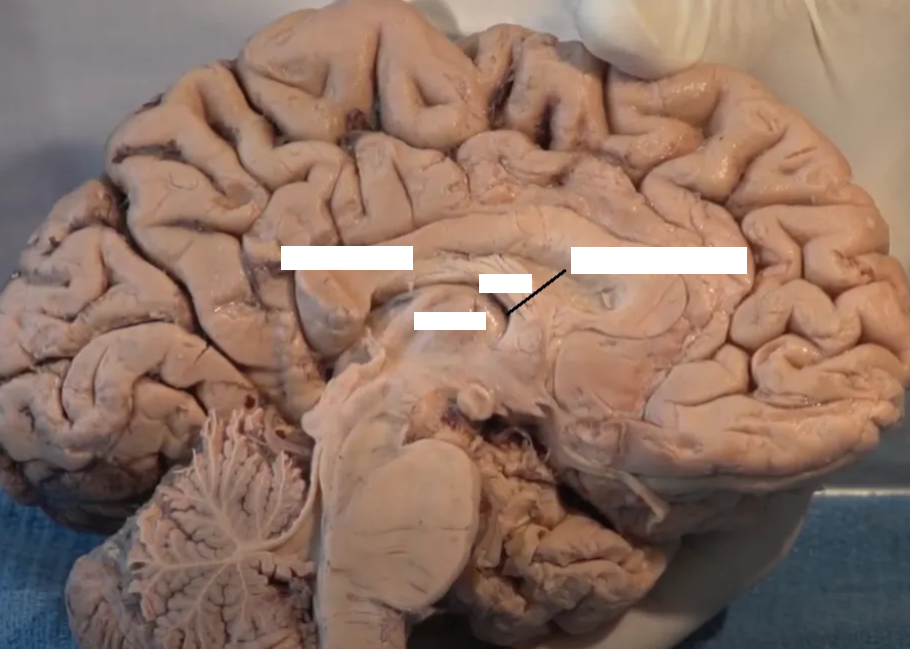

Thalamus (pink) and hypothalamus (yellow): their medial surfaces border the third ventricle (blue).

Overlaying the green cingulate and parahippocampal gyri with the purple hippocampus highlights the limbic lobe. Yellow = fornix. Brownish pink = hypothalamus

The purple hippocampus is visualized tracing the ventricular system (turquoise).